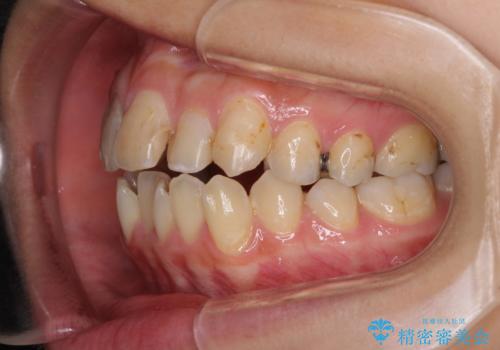

後戻りを治したい 骨格的なズレの大きい方のインビザライン矯正

- 中学生の時に矯正治療をしたものの、後戻りを気にして来院された患者様です。

骨格的に下顎が右側に変位しているため、左右の咬み合わせを理想的なものに改善することはできませんが、インビザラインにて歯列を整えることとしました。

骨格的なズレによる左右差は改善できませんでしたが、上下の正中を極力合わせるようにすることができました。